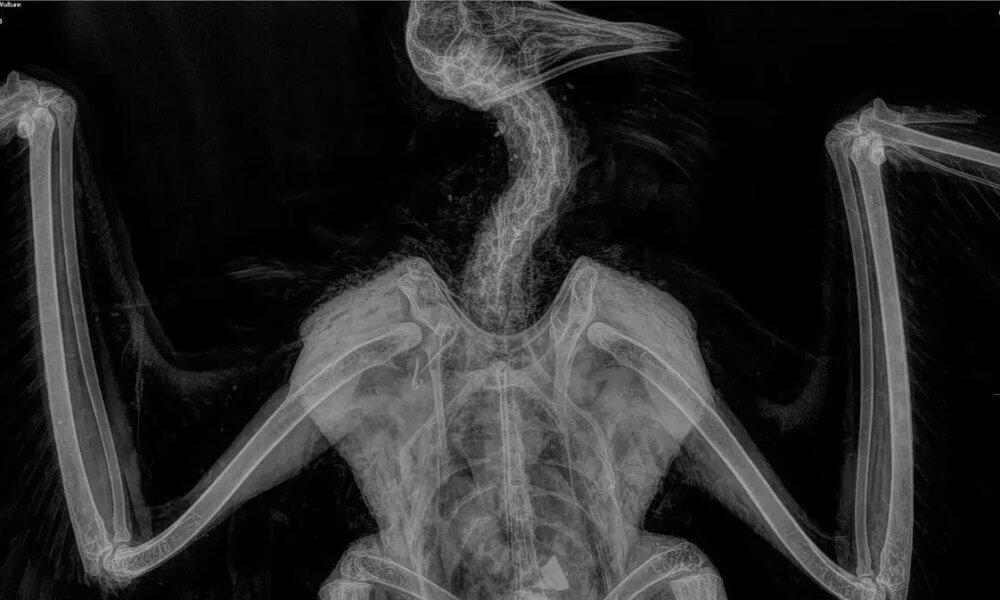

בחברה להגנת הטבע, מציינים כי הרחם שנפגע, הוא פרט צעיר, יליד 2024, שאיננו מקנן עדיין, אך שרד את שנתו הראשונה והיה בדרך להצטרף לאוכלוסייה שדוגרת בישראל....